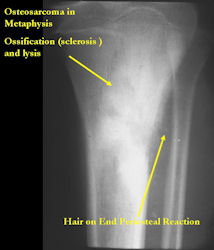

Gross Pathology: Conventional Osteosarcoma

These are examples of the gross pathology specimens of resected conventional osteosarcoma, consisting of both bony and soft tissue areas. X-rays of the specimens are included.

- Osteosarcomas are composed of ossified or non-ossified tissue

- Ossified tissue is yellow-white and hard

- Less ossified tissue is soft and less yellow

- Non-ossified tissue is tan and fleshy

- Most (95%) of conventional osteosarcomas penetrate the cortex and form a large extraosseous soft tissue mass

- The lesion permeates the marrow spaces

- Osteosarcomas usually infiltrate the marrow several centimeters away from the main tumor mass

- Skip lesions may be apparent that are separated from the main tumor by normal marrow

- Osteosarcomas may also have cartilaginous components that appear as translucent lobules, and/or fibrous components that are tan, soft to firm rubbery areas

- Osteoblastic areas are usually white to yellow, firm, hard and gritty

- The consistency of the tumor depends on the amount of osteoid deposition, cartilaginous and fibrous areas

- Foci of hemorrhage and necrosis are common

- Periosteal reactions such as the Codman’s triangle are apparent at periphery of soft tissue mass

- Osteosarcomas rarely penetrate the growth plate grossly

- Invasion of the joint is uncommon but can occur by cortical penetration, joint capsule extension, or extension along cruciate ligaments